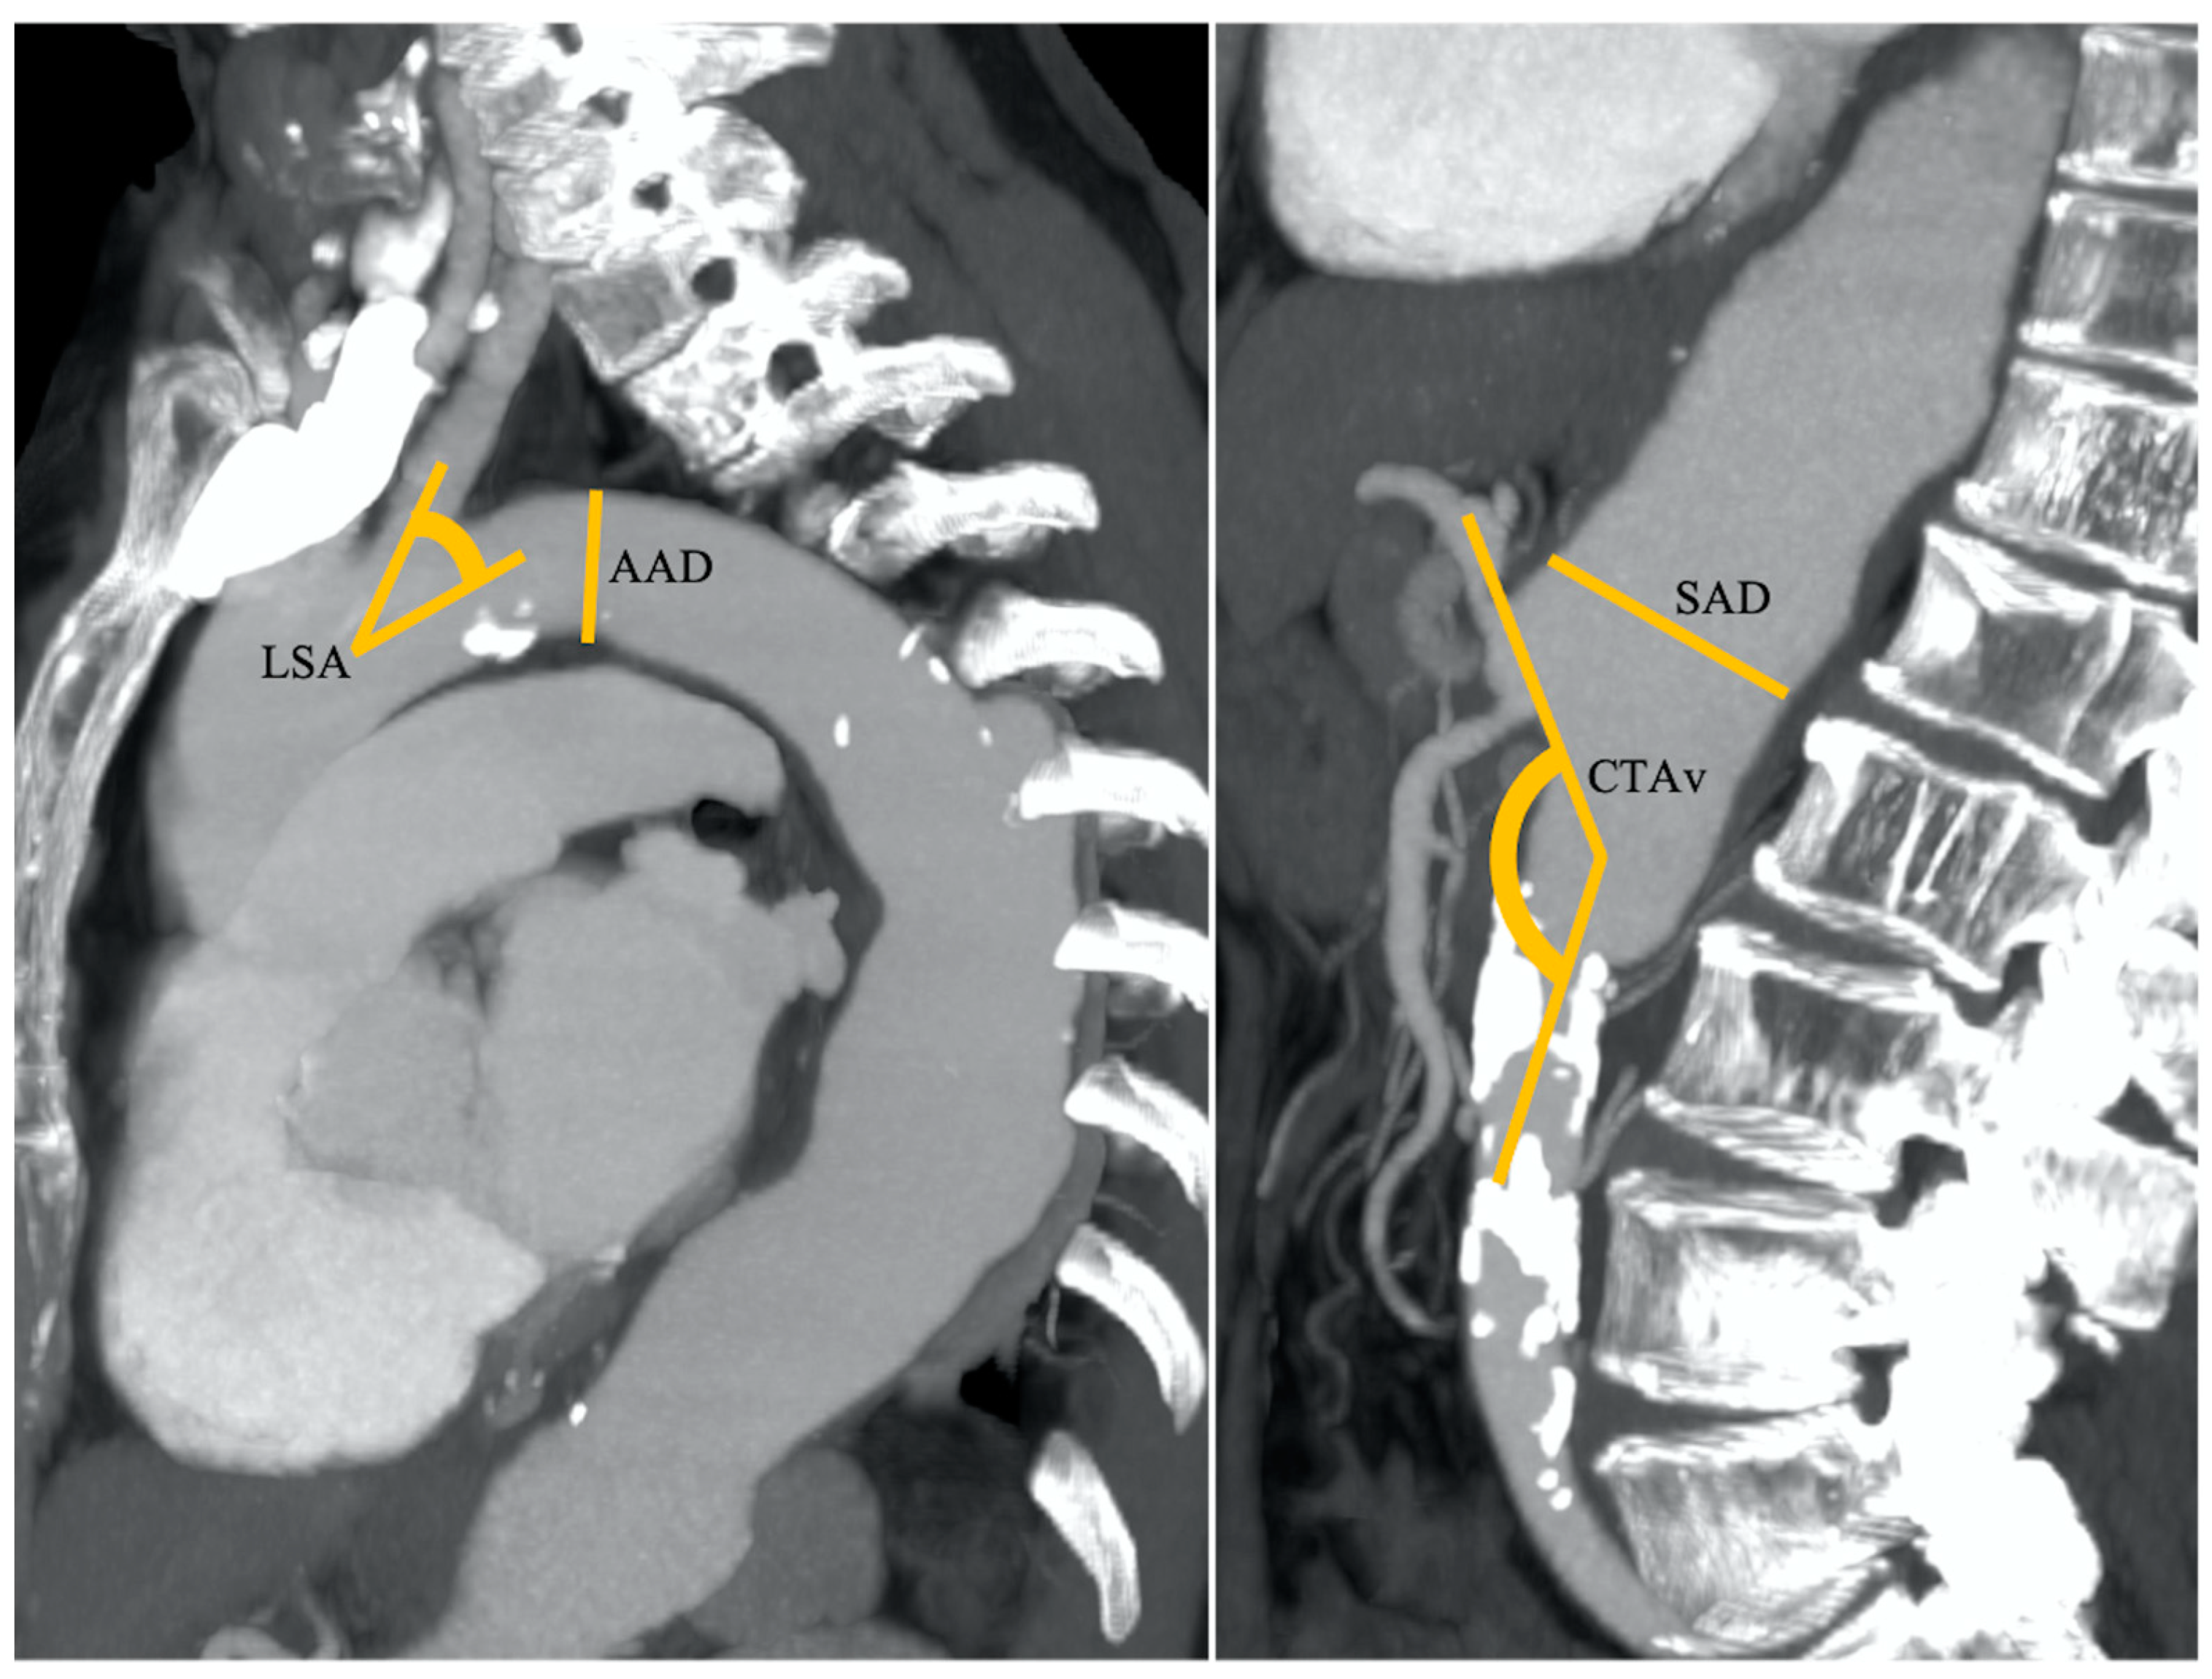

Figure 2. An 83-year-old patient with nodular HCC in the right liver lobe with a radial diameter (RD) of 2 mm (not shown) (0 points), left subclavian artery angle (LSA) of 45° (1 point), an aortic arch angulation (AAA) type III (1 point) with a diameter (AAD) of 32 mm (1 point), suprarenal aorta diameter (SAD) of 40 mm (1 point), and celiac trunk angle (CTA) of 130° (1 point). Final RAD-access score: 5, transfemoral access preferred for values between 3 and 6.